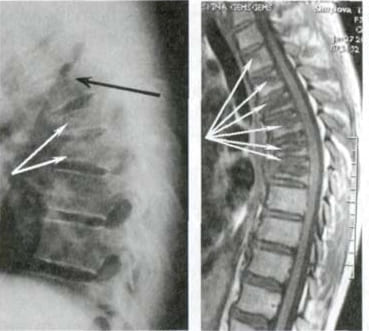

Veja esta radiografia. É a coluna vertebral de um homem de 44 anos, mas parece... a de um idoso. Antigamente, este tipo de lesão manifestava-se mais tarde, a partir dos 60 anos, mas hoje em dia é muito comum em pessoas com cerca de 40 anos. Estas alterações progridem com a idade e ignorá-las pode levar à perda total da mobilidade.

Coluna vertebral de um paciente de 44 anos: tudo começou com uma simples dor, mas numa semana surgiu uma hérnia e, em duas semanas, um deslocamento das vértebras, compressão do nervo e necessidade de cadeira de rodas.

Uma das poucas soluções que a ciência médica pode oferecer é uma cirurgia complexa e arriscada para remover a hérnia e colocar pinos metálicos. Mas pense bem! Mesmo os melhores cirurgiões reconhecem que a cirurgia da coluna vertebral é uma medida extremamente imprudente e perigosa, que muitas vezes leva a problemas mais graves, infecções, complicações e até mesmo à morte.

A remoção da hérnia da coluna vertebral com pinos metálicos é um procedimento que muitas vezes pode causar inúmeras complicações: o risco de infecção, amputação ou sépsis aumenta em 60%. O processo de recuperação é longo e doloroso, com um risco significativo de incapacidade.